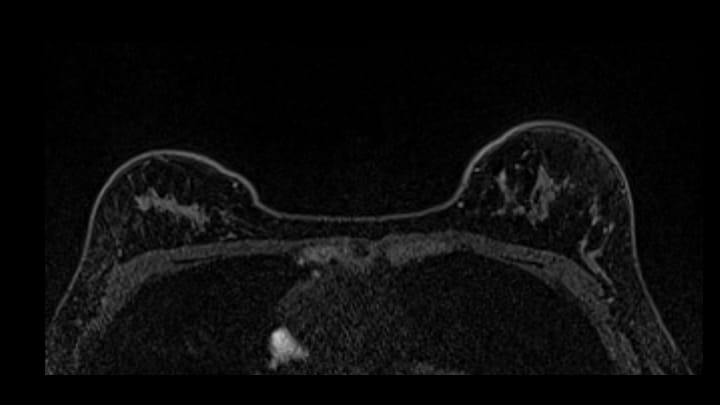

8. ダイナミックMRI 後期相

早期相と同様に右乳腺上部にnon-mass enhancementあり。